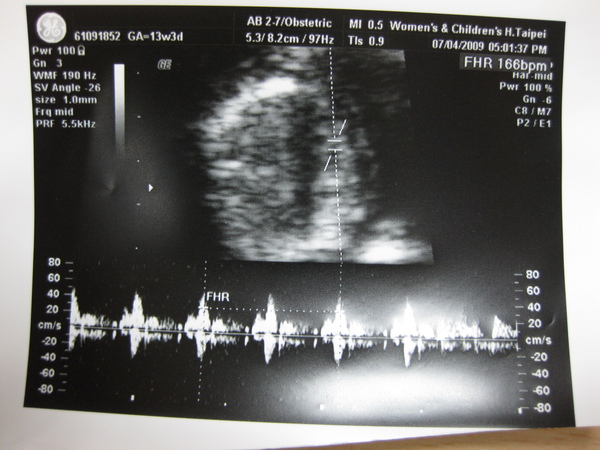

2009.07.04 婦幼醫院 頸部透明帶 14W_4D